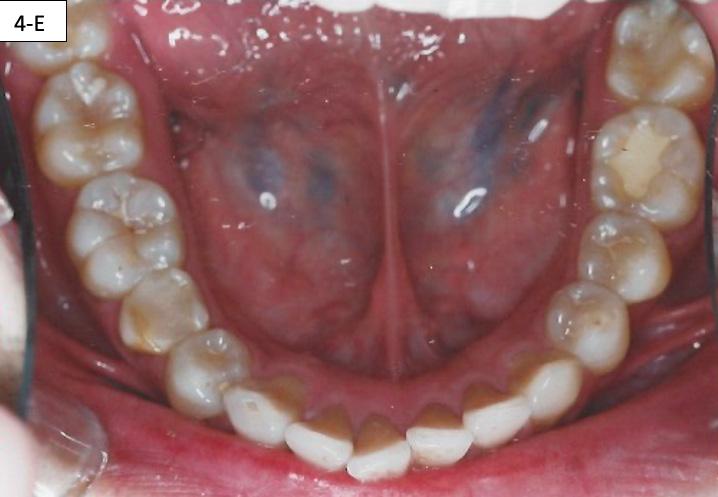

FIG. 4E: Mandible occlusal view

Clinical dental appraisal revealed full Angle Class II molar and cuspid relationship. The arches were wide and there was a moderate crowding. The patient had 9.0 mm overjet and 6.0 mm overbite. However, the patient reported SDB symptoms, and he also presented with symptoms and signs of TM dysfunction (Figure 4A, B, C, D, E, F))